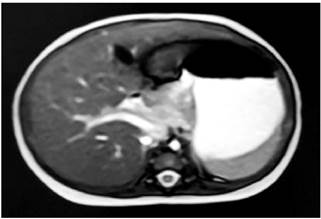

La ecografía abdominal evidenció el colédoco de 2,6 mm, sin otros hallazgos. Se solicitó una colangiorresonancia con vesícula biliar colapsada con longitud de 21 mm y diámetro transversal de 3 mm, sin dilatación de la vía intrahepática; la vía extrahepática no se pudo caracterizar por una limitación técnica (Figura 1). Se realizó una colangiografía intraoperatoria que reportó atresia de vías biliares y, posteriormente, se realizó la derivación biliodigestiva tipo Kasai a los 95 días de vida.